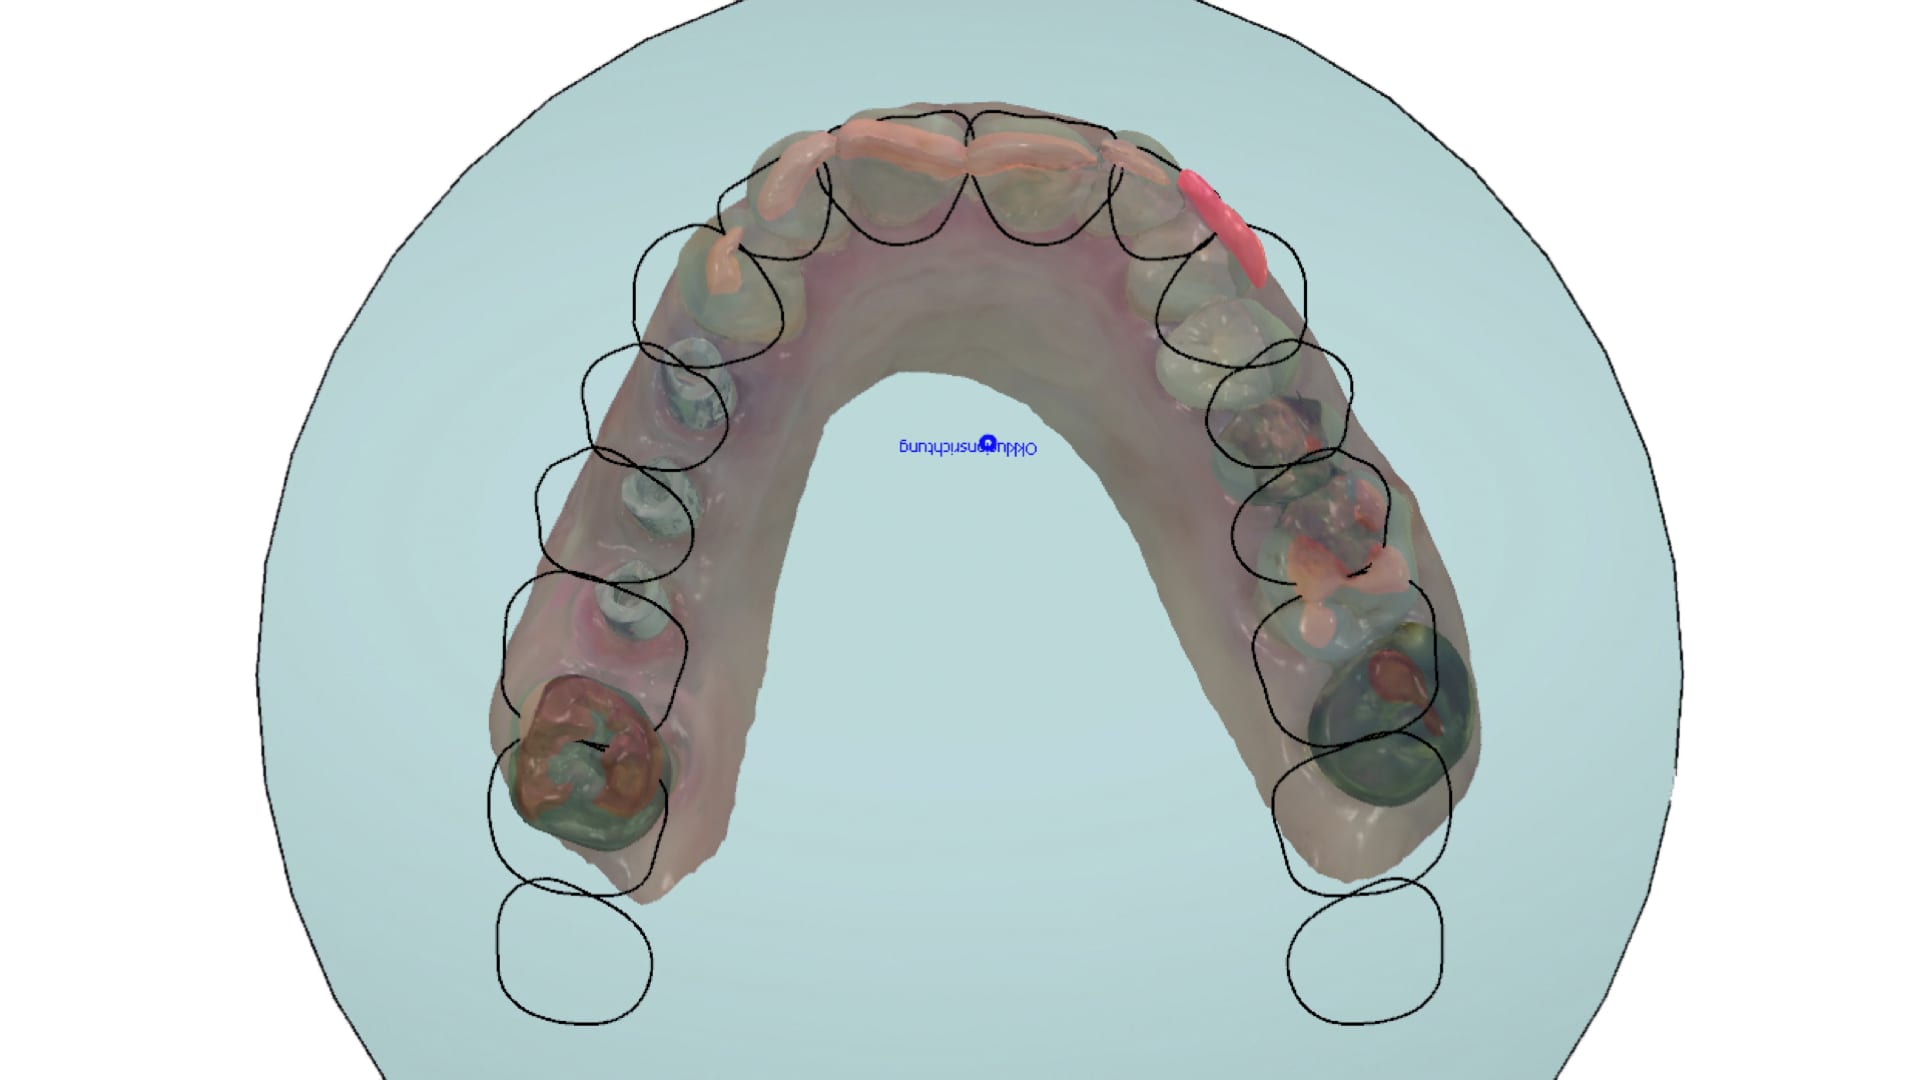

Abb. 5: Intraorale Scandaten vom Oberkiefer

Der Workflow ergibt sich aus der Programmierung. Als erster Schritt erfolgt die Datenbereinigung. Hierbei entfernt der Techniker nicht-relevante Bereiche des Scans sowie mögliche Artefakte. (Abb. 5 und 6) Er richtet die Scans im virtuellen Artikulator ein und legt somit bereits den Grundstein für die folgende digitale Modellverarbeitung (Abb. 7). Im folgenden Schritt werden die mit dem 3Shape Trios 3 intraoral erfassten Scanmarker mit den in der Dental Designer Software hinterlegten DME-Dateien registriert. Hierbei ist besondere Präzision gefordert. Wird der Scanmarker nicht präzise registriert, ist die virtuelle Implantatposition nicht richtig dargestellt und die gefertigte Prothetik wird nicht passen. Softwareseitig stehen dem Nutzer zwei Arten der Registrierung zur Verfügung: die Ein-Punkt- und die Drei- Punkt-Registrierung. Je nach eingesetztem Scanmarker erweist sich die eine oder andere Variante als vorteilhafter. In dem gezeigten Fall erfolgte die Registrierung im Drei-Punkt-Verfahren. Die Software erzeugt im Anschluss automatisch die hinterlegten Datensätze der Modellanaloge und die in der Auftragsanlage ausgewählten Abutmentgeometrien in ihrer jeweilig korrekten Position. Die Ausformung des Emergenzprofils sowie die finale Gestaltung der Abutments werden im Dental Designer mittels Backward-Planning erstellt, das heißt, die zu versorgenden Zähne werden im ersten Schritt vollanatomisch in ihrer finalen Form und Ausdehnung modelliert. Danach arbeitet der Zahntechniker „rückwärts“ und erzeugt so die optimalen Abutments in Abhängigkeit des digitalen Wax-ups sowie die exakt reduzierten Zirkonoxid-Gerüste.